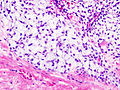

Microscopic

- "Abnormal cartilage":

- +/-Nuclear atypia - high grade lesions.

- High grade lesions:

- Nuclear clearing.

- Nucleoli.

- Hyperchromasia.

- Low/intermediate grade lesions:

- Bi-nucleation.

- Hypochromatic enlarged nuclei.

- Infiltration of lamellar bone ("invasion") - not common - diagnostic.

- Increased cellularity.

- More cellular than cartilage... but relatively paucicellular compared to other sarcomas.

- Irregular spacing of chondrocytes.

Notes:

- Low grade chondrosarcoma are not cytologically malignant; the diagnosis rests mostly on radiologic findings.

- The exception is infiltration of lamellar bone -- this is diagnostic of chondrosarcoma.[8]